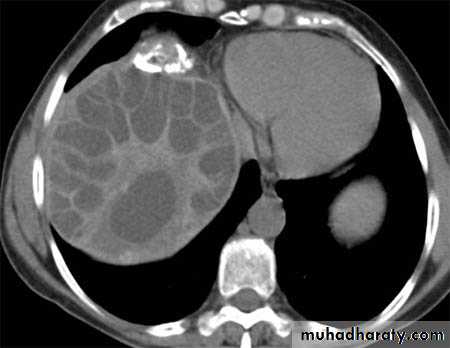

Hydatid cyst within the liver

CT Scane

Hydatid cyst

Appear as large oval hypo dense area density of fluid with well defined margin , sometime at their periphery multiple flecks of calcification are seen at their periphery .

Hydatid cyst with daughter cyst , appear as multiple hypo densities rounded area within the main loculi with multiple rim of

calcification